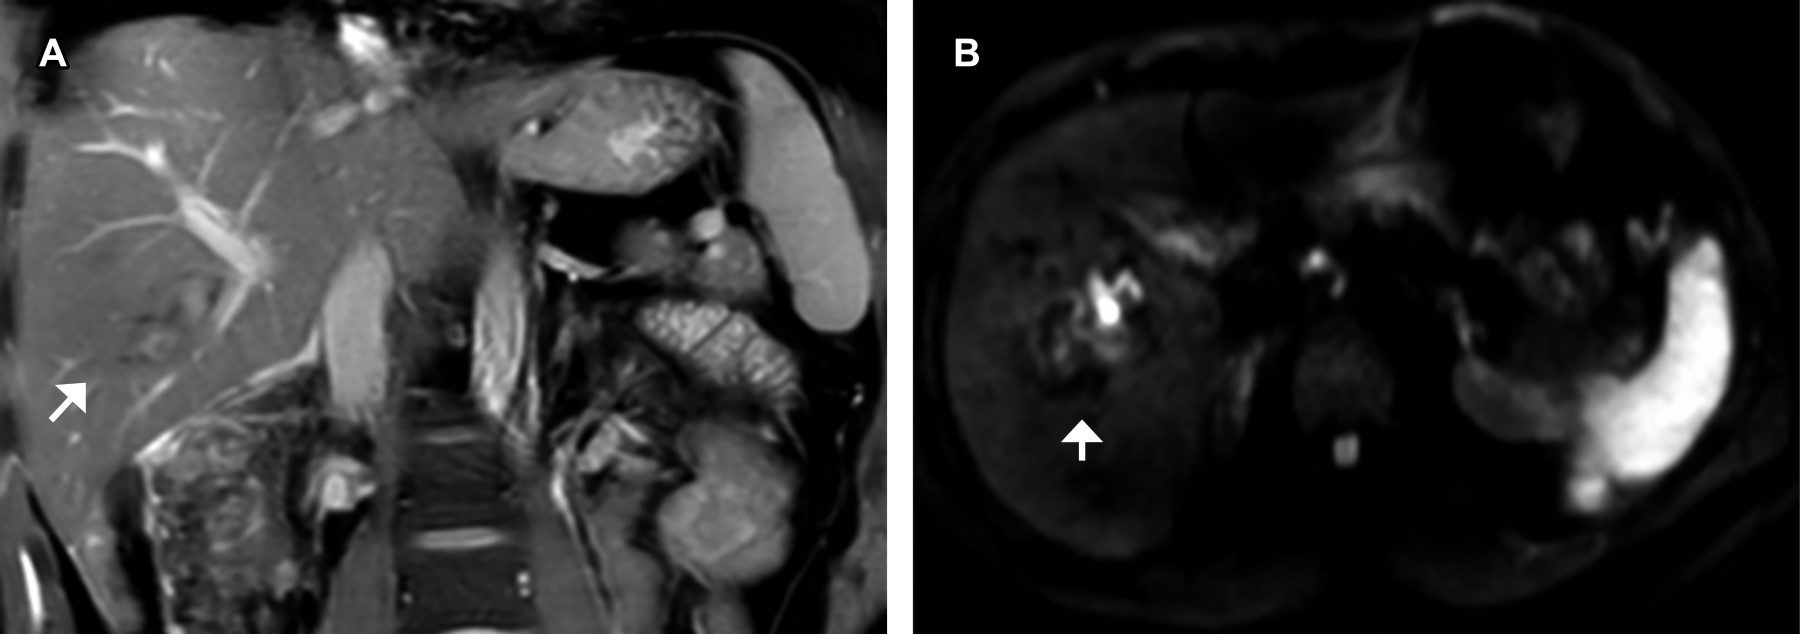

This is a 30-year-old male patient who, after suffering a three-story fall, showed hepatic contusion on CT scan and ultrasound. MRI with gadoxetic acid demonstrated laceration, vascular integrity, and biliary anatomy without evidence of injuries.

Figure 2